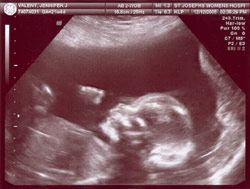

Матка женщины расширяется, подготавливаясь к росту ребёнка. У него формируются глазницы, есть ушные раковины, видны руки, на которых есть крохотные пальчики, видны ступни, также есть маленький хвостик, который потом исчезнет. Идёт развитие внутренних органов (лёгких, печени, почек, органов пищеварения). К 8 недели беременности рост крохи достигнет примерно 2,5 см. Глаза ребёнка прикрыты веками, которые остаются закрытыми до 24 недель.

К 12 неделям беременности матка уже немного выступает над плоскостью таза. К этому времени ребёнок уже достигает в длину до 9 см. Тело очень выросло, но головка всё еще очень велика по сравнению с ним. На пальцах рук и ног появляются ногти. Ребёнок начинает глотать околоплодную жидкость. В это время ребёнок уже даже может пописать в околоплодный пузырь.

Рост ребёнка к концу 4 месяца достигнет примерно 18 см. Тельце ребёнка имеет красноватый цвет из-за просвечивающих сквозь тонкую кожу кровеносных сосудов. Уже явно определяется пол ребёнка. В организме ребёнка формируется собственная иммунная система. Почки уже функционируют, печень вырабатывает желчь. Образовались суставы рук и ног.

Длина тела к концу этого месяца достигает 25 см. Кожа менее прозрачна с пушком, который покрывает всё тело малыша. Ребёнок сжимает и разжимает кулачки. Начинают работать селезёнка и все эндокринные железы. К этому времени малыш уже даже умеет выражать эмоции. Он строит гримасы, в числе которых можно различить и улыбку.

Длина ребёнка к концу 6 месяца достигает 32 см. Кожа покрыта морщинками из-за недостатка жировой прослойки. С этого месяца начнут откладываться жировые слои. Мышцы крохи хорошо развиваются. Начинают созревать лёгкие, но они ещё не могут обеспечить нормальную жизнедеятельность. Ребёнок умеет кашлять и икать. Он хорошо слышит мамин голос. На языке уже достаточно хорошо развиты вкусовые рецепторы. Глазки могут реагировать на свет и темноту.